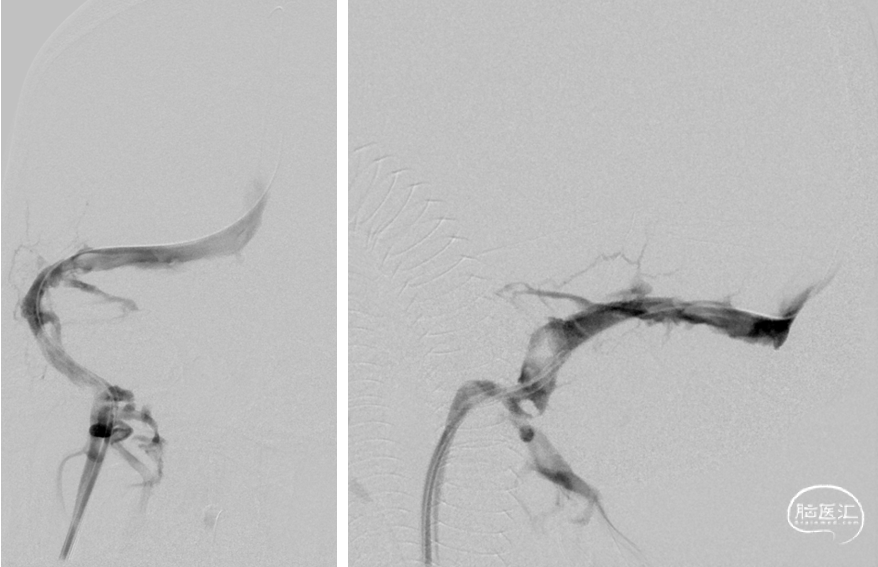

DSA(2022-1-6)

右侧颈总动脉造影示:上矢状窦显影模糊,右侧横窦、乙状窦未见显影,静脉回流缓慢。穿刺右侧颈静脉,留置8F血管鞘,全身肝素化,50万尿激酶入动脉滴注。

术前DSA